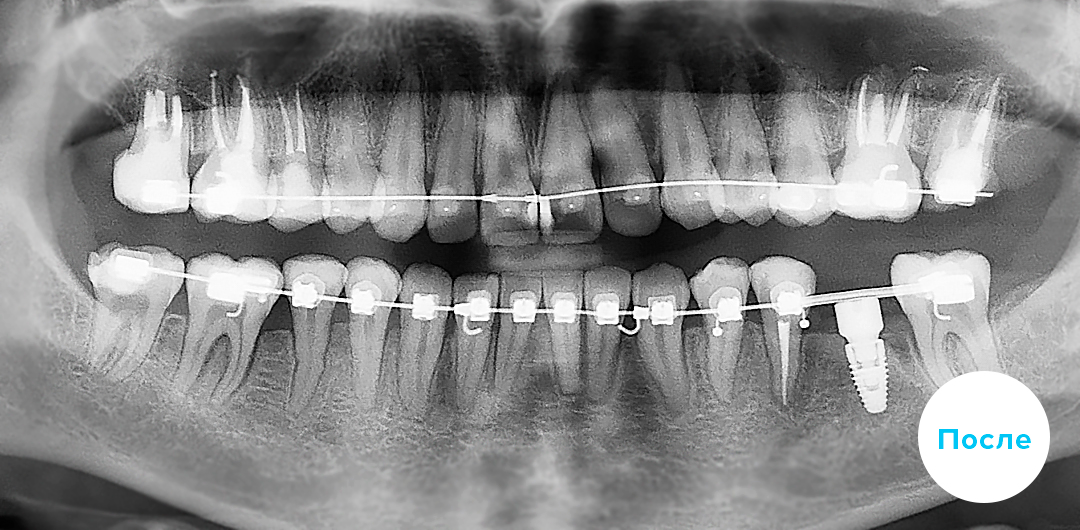

Лечение дистального прикуса и подготовка к протезированию

В приведенном клиническом случае ортодонты использовали цифровую брекет-систему INSIGNIA на базе самолигирующих брекетов Damon Clear/Q

До

После

Срок лечения:

26 мес

Возраст пациента:

28 лет

До

После

Клинический случай

Подробнее о лечении:

Исправление дистального прикуса с применением цифровой брекет-системы INSIGNIA на базе самолигирующих брекетов Damon Clear/Q и подготовка к протезированию